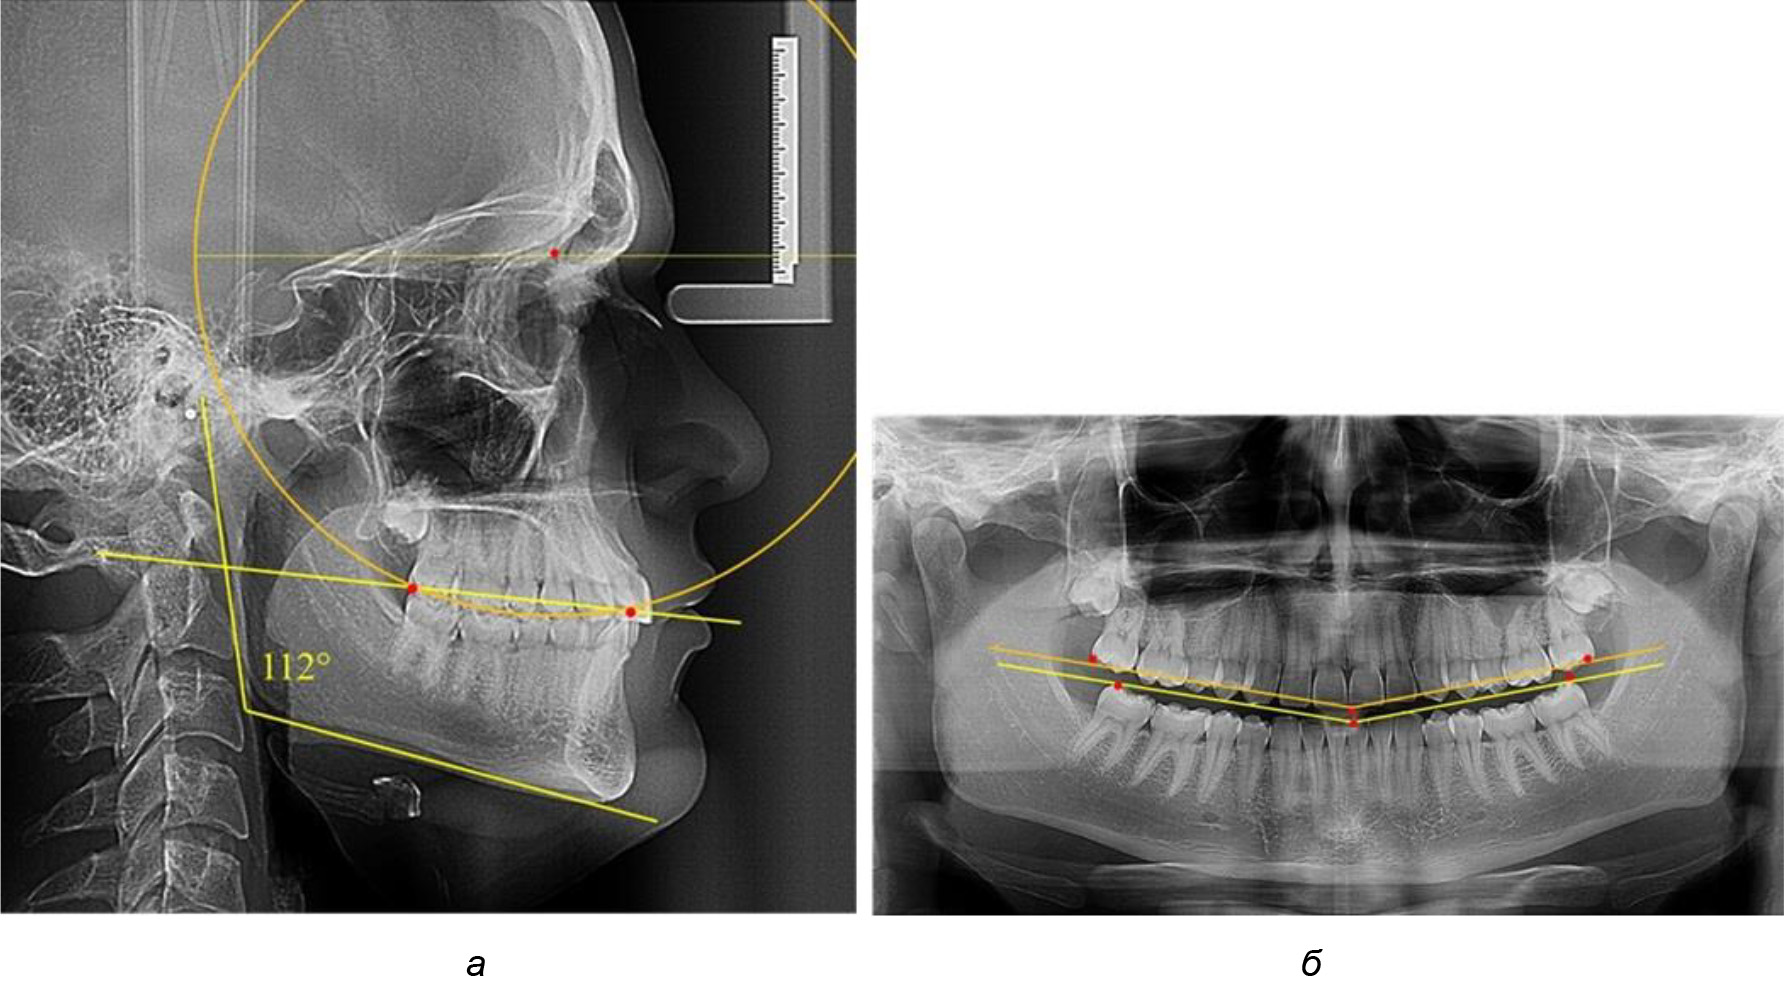

У людей с аномалиями окклюзии по сагиттали в 1-й подгруппе обследовано 9 человек. Обращает на себя внимание увеличение глубины кривой Spee, что нами расценивалось, как патологическая форма кривой линии окклюзии.

Глубина кривой Spee в среднем по 2-й подгруппе составила (5,69 ± 1,57) мм, что было достоверно больше, чем у людей с физиологической окклюзией (р ˂ 0,05). Достоверных различий с показателями, полученными при анализе ТРГ и ОПТГ, нами не отмечено (р ˃ 0,05). Отношение радиуса окружности к сагиттальному размеру окклюзионной линии в среднем по подгруппе составляло 1,372 ± 0,042 и не соответствовало числу Фибоначчи, что может быть использовано в качестве диагностического критерия определения патологической формы кривой Spee. После лечения пациентов техникой «прямой» дуги было отмечено незначительное увеличение сагиттального размера окклюзионной лини в среднем на (2,12 ± 0,77) мм. Однако окклюзионная линия практически касалась окклюзионного контура всех жевательных зубов, и отмечалось практически полное отсутствие кривой Spee.

Таким образом, проведенное лечение техникой «прямой» дуги способствует нормализации окклюзионного равновесия и торку передних зубов, однако не соответствует оптимальному окклюзионному статусу, характеризующему физиологическую окклюзию. При этом величина нижнечелюстного угла оставалась на прежнем уровне (рис. 5).

Рис. 5. Особенности ТРГ при патологической кривой Spee до лечения (а) и после лечения (б) техникой «прямой» дуги

Обращает на себя внимание, что глубина кривой Spee в анализируемой подгруппе практически не отличалась от показателей, полученных у людей с физиологической окклюзией, и составляла (4,23 ± 1,58) мм. Отношение радиуса окружности к сагиттальному размеру окклюзионной линии в среднем по подгруппе составляло 1,623 ± 0,02 и соответствовало числу Фибоначчи.

После лечения пациентов техникой «прямой» дуги, так же как и в 1-й подгруппе, было отмечено увеличение сагиттального размера окклюзионной лини в среднем на (2,38 ± 0,83) мм. Окклюзионная линия практически касалась окклюзионного контура всех жевательных зубов, и отмечалось практически полное отсутствие кривой Spee, так же как и у людей 1-й подгруппы 2-й группы (рис. 6).

Рис. 6. Особенности ТРГ при оптимальной кривой Spee до лечения (а) и после лечения (б) техникой «прямой» дуги

Таким образом, проведенное лечение техникой «прямой» дуги способствует нормализации окклюзионного равновесия и торку передних зубов, однако не соответствует оптимальному окклюзионному статусу, характеризующему физиологическую окклюзию. При этом величина нижнечелюстного угла оставалась на прежнем уровне.